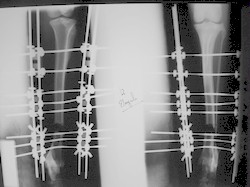

PRÁCTICAS CURSO DE FIJACIÓN EXTERNA PERFECCIONAMIENTO.

Elongacion.